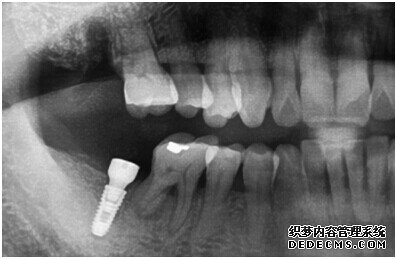

牙齿拍片初步检查

刘女士牙齿拍片初步检查

由CT片检查来看,刘女士口腔健康环境还是很好的,牙槽骨也适合种植牙的条件,而且由我们最后一颗牙是非常重要的,经过专家的建议和详细解释了原因之后,刘女士选择了美国百康种植牙。

成功植入种植体后的效果图

种植体成功植入后的CT效果图